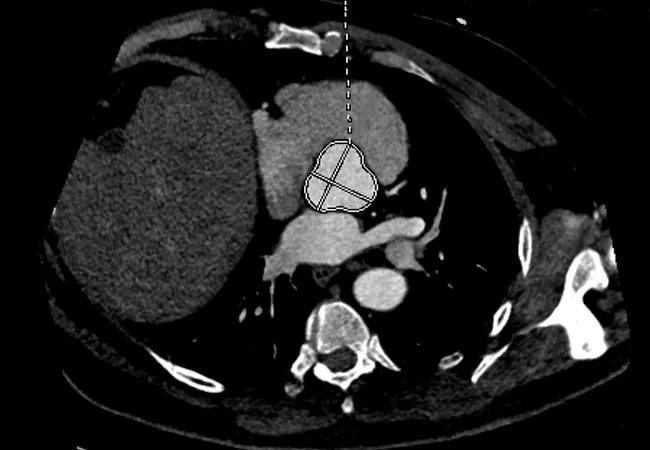

Sample cross-sectional image from a patient with a trileaflet aortic valve and a dilated aortic root. This patient’s ratio of aortic root cross-sectional area to height was 10.4 cm2/m.

The ratio of aortic root area over height was calculated for all patients, and a cutoff of > 10 cm2/m (based on the earlier reports mentioned above) was designated abnormal. Patients were followed for a mean of 7.3 ± 2.6 years, during which all-cause death rates were tracked.